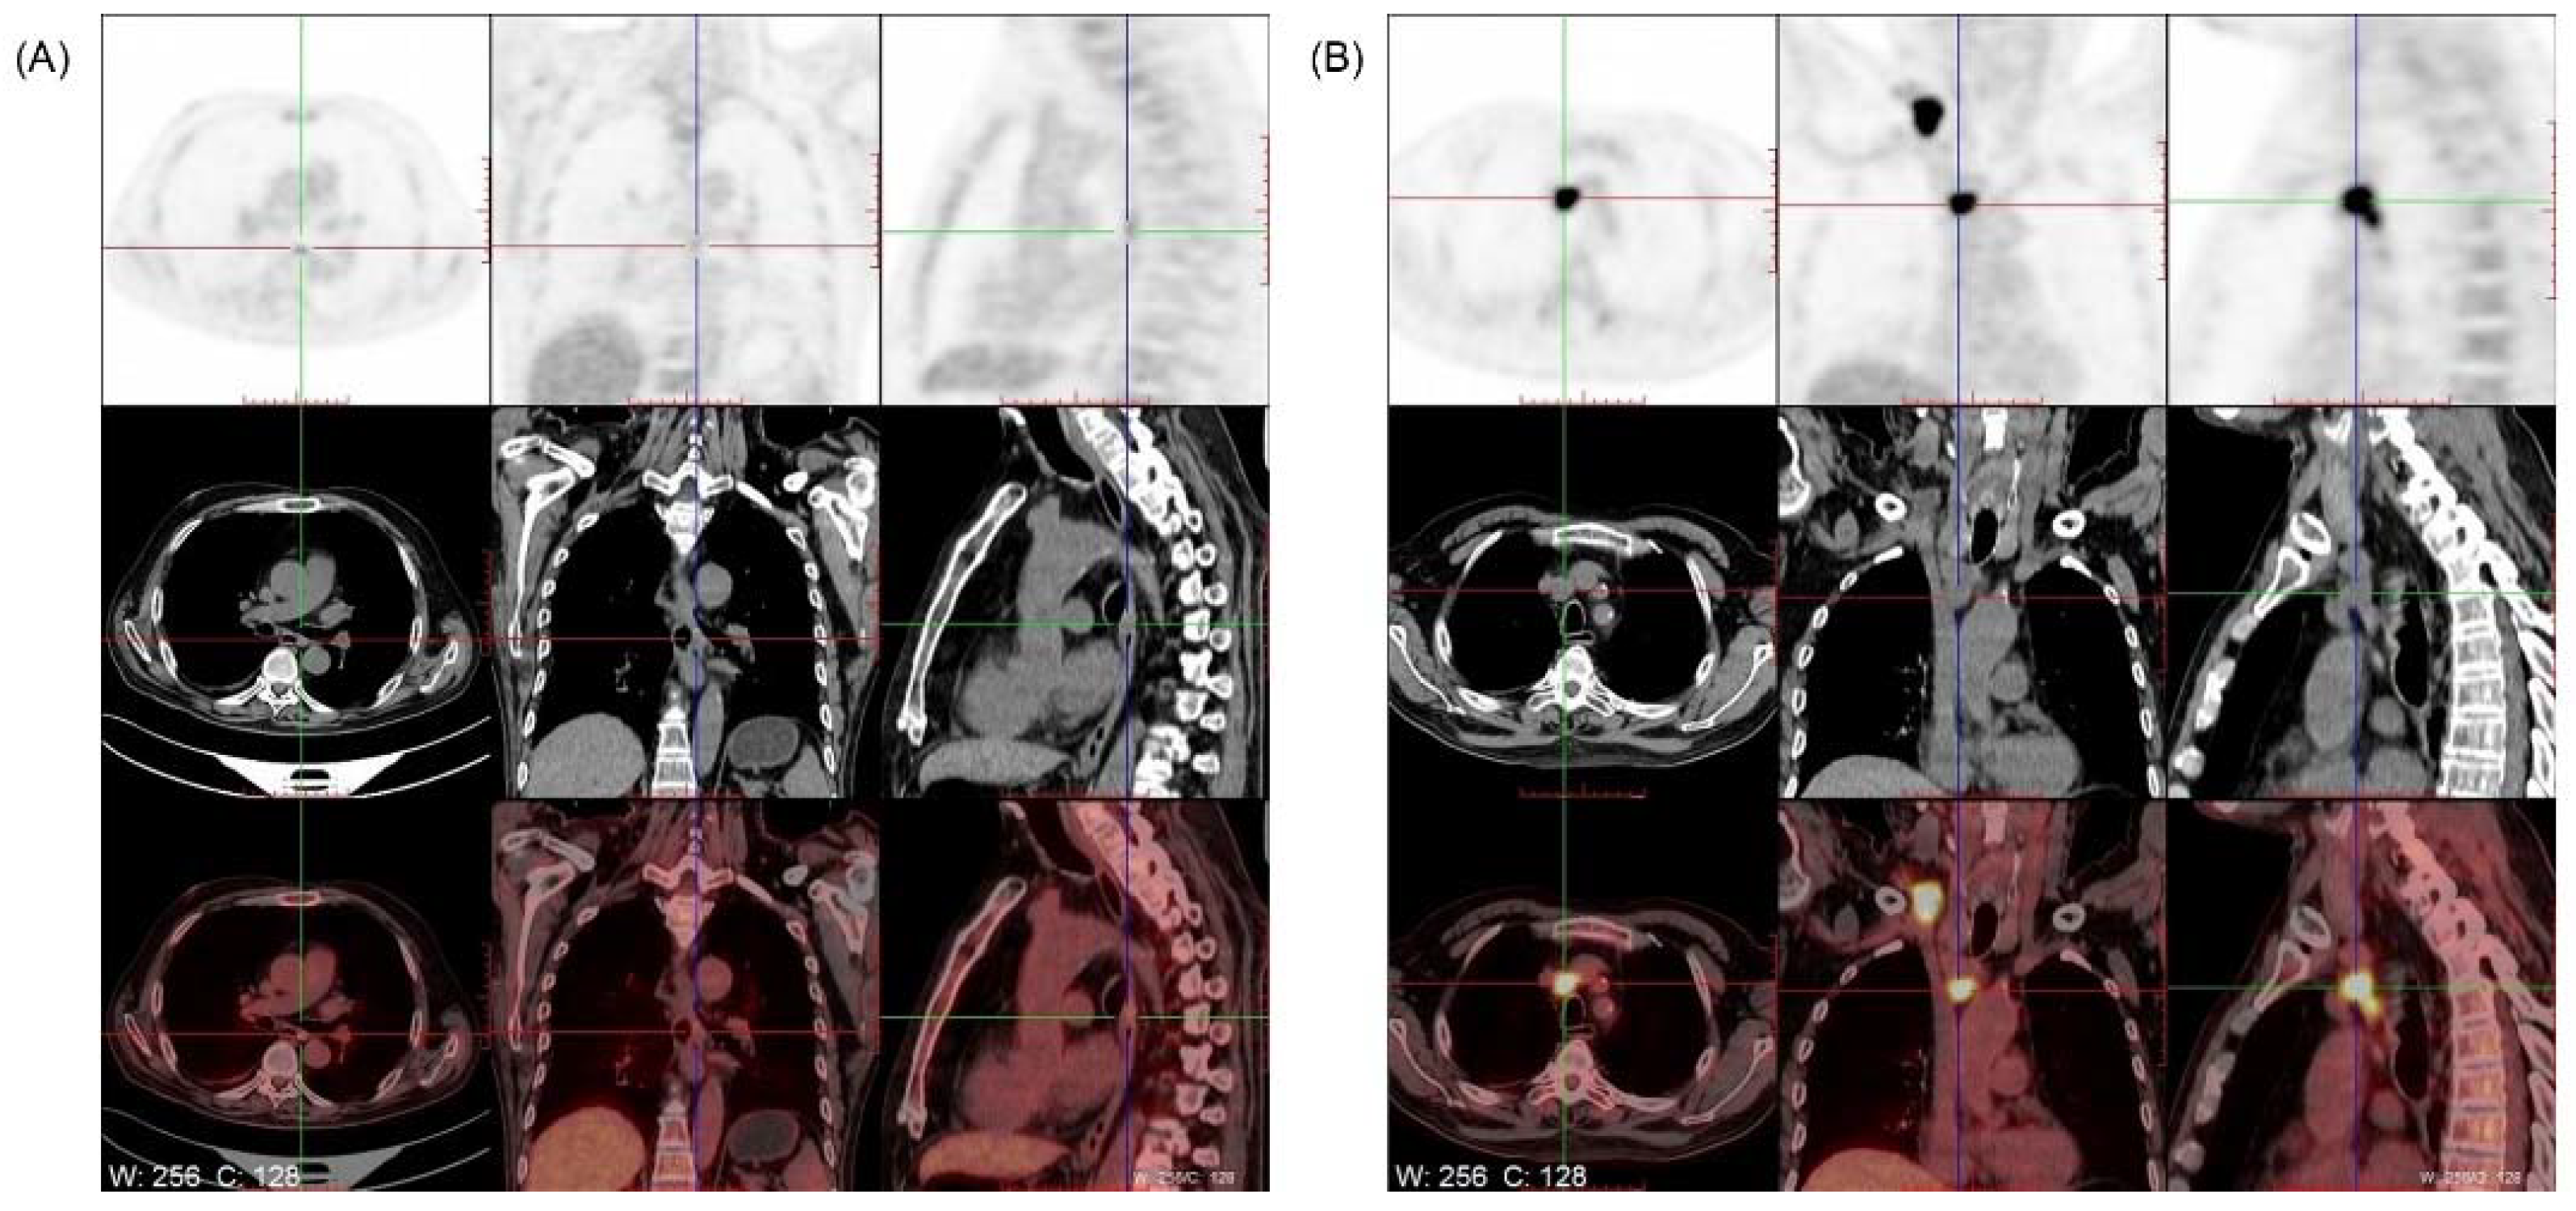

2. Case Presentation